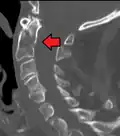

A fracture of the base of the dens as seen on CT -